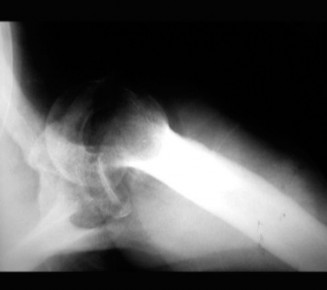

Rotator cuff tears are a common reason for shoulder pain and a common reason to obtain shoulder imaging. As a result, numerous different imaging modalities exist offering different pros and cons. Plain films are still the initial imaging modality of choice. These are most useful in ruling out other possible diagnosis but can help with the diagnosis of a rotator cuff tear as well. Changes to the tendon itself

may appear as calcific tendinosis, which would most commonly be seen at the bone–tendon interface. A decrease in the acromiohumeral distance (less than 2 mm) may also be indicative of a cuff tear. In late cases of rotator cuff tears, superior subluxation of the humerus may be evident. Certain variations in acromial anatomy, including spurs or a hook-shaped (type 3) acromions, may be associated with rotator cuff tears as well. With progression of rotator cuff tears, degenerative changes including spurs, cysts, and sclerosis may be evident at the greater tuberosity. In late, massive tears one may see degenerative changes consistent with rotator cuff arthropathy.